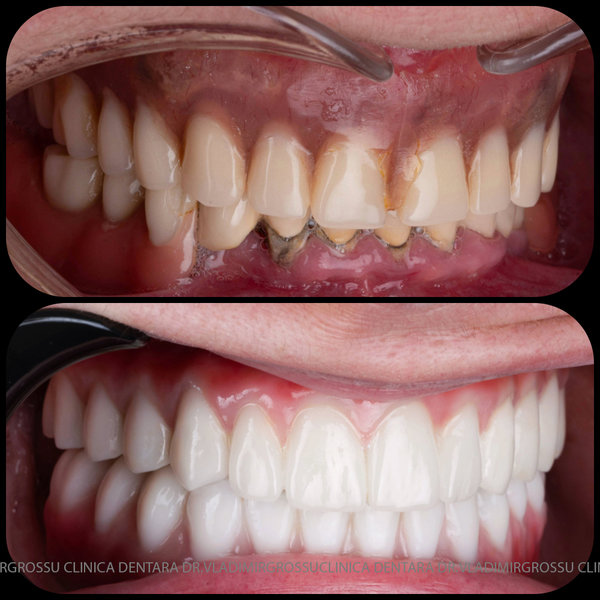

Această metodă este recomandată pacienților edentați total sau celor cu lipsuri dentare multiple. Procedura se realizează într-o singură etapă, iar pacientul primește proteza provizorie în ziua următoare intervenției. De regulă, proteza provizorie este realizată din masă plastică frezată. Suturile se îndepărtează după 5-7 zile.

La aproximativ 6 luni de la prima etapă, pacientul revine pentru protezarea definitivă. În această fază, medicul lucrează la nivelul multiunit-urilor și nu direct pe implanturi, ceea ce reduce riscurile pentru implant în etapa protetică.